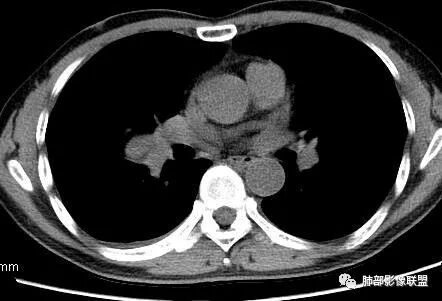

3.肿块常常较大,甚至巨大,病灶边界一般清楚,影像上常有假包膜样结构、有膨胀性生长的特点,影像科医师有时甚至会纠结其来源于肺部或是胸壁纵隔。常见的肺癌肿块,很少有机会能长成这样的规模。

5.病灶密度大多不均,不规则坏死液化,少数病例出现钙化。增强扫描常观察到由外而内的厚壁不均匀强化,中央半岛样强化等等,厚壁中或实性区常能显示血管影。一些病灶中央呈现边界清楚囊样变。

7.可以出现血行转移,但较少出现肺门纵隔淋巴结转移。

8. 需要鉴别的是大细胞肺癌,也有病灶光整,周边干净的特点,但大细胞癌常常密实,均匀,很少能长成巨块。

9.此外肺边缘生长的肉瘤尚需与孤立性纤维瘤相鉴别。